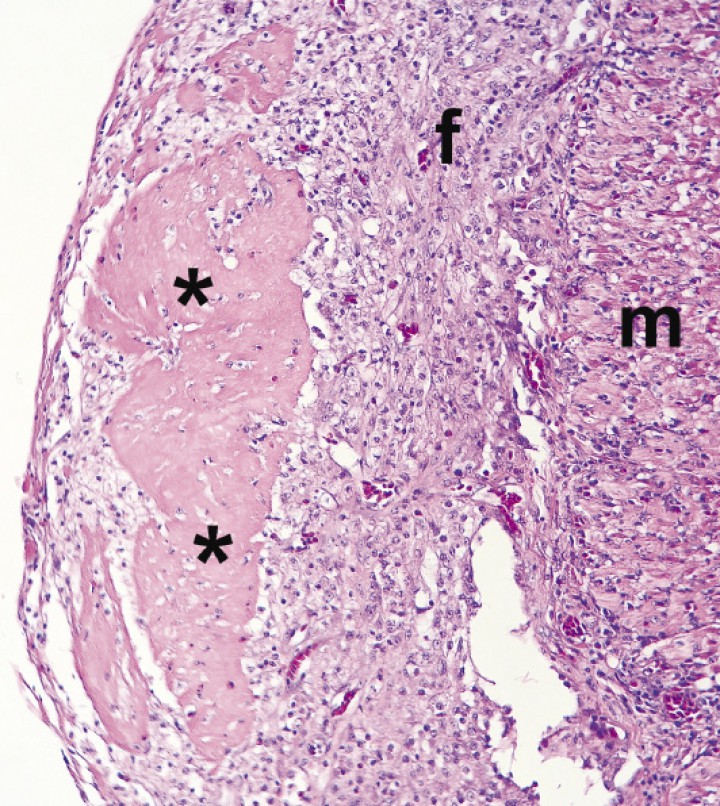

El estudio radiológico, realizado bajo anestesia general inhalatoria con isofluorano (IsoVet, Braun, Morpeth, Reino Unido) y oxígeno con mascarilla (inducción al 5% y mantenimiento al 3%), reveló un marcado aumento de la silueta hepática, además de un incremento de la radiodensidad en el campo pulmonar (Fig. 1).

<p>Proyección ventrodorsal de todo el cuerpo. Se observa hepatomegalia con silueta redondeada, así como un incremento difuso de la opacidad de ambos pulmones.</p>

Proyección ventrodorsal de todo el cuerpo. Se observa hepatomegalia con silueta redondeada, así como un incremento difuso de la opacidad de ambos pulmones.

<p>Imagen microscópica del epicardio. El pericardio visceral está engrosado debido a depósitos de fibrina (asteriscos) rodeados de tejido conjuntivo fibroso (f). m = miocardio. (Hematoxilina-Eosina x20).</p>

Imagen microscópica del epicardio. El pericardio visceral está engrosado debido a depósitos de fibrina (asteriscos) rodeados de tejido conjuntivo fibroso (f). m = miocardio. (Hematoxilina-Eosina x20).